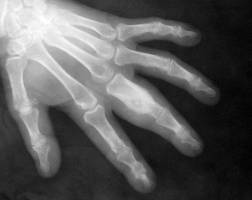

CONDROMUL

Aspectul radiologic depinde de localizarea tumorii dar exista câteva caractere comune: prezinta o zona de osteoliza cu contur net, cu fine supturi sau zone intens calcificate.

Encondromul falangelor si metacarpienelor duce la deformarea oaselor, subtierea corticalei si largirea osului.

Eccondromul prezinta zone de osteoliza marginala, deseori multiple. În jurul acestor zone nu se constata nici osteoscleroza nici atrofie osoasa.

Diagnosticul diferential trebuie facut cu spina ventoza, chistul osos esential, tumora cu mieloplaxe, osteita fibroasa.